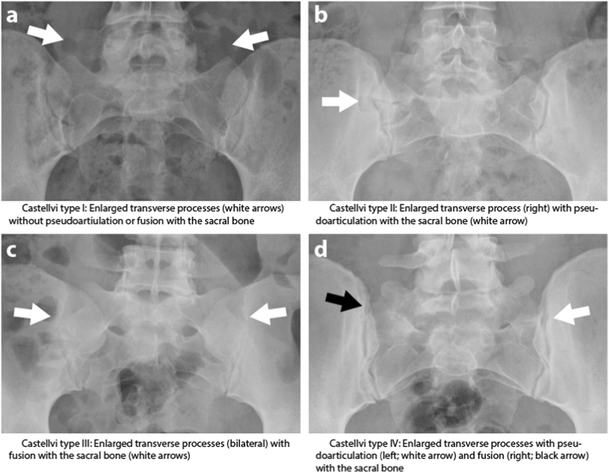

This is likely l5 with partial fusion of the right transverse processthere is suggestion of a pseudojoint which can be a source of pain. In 1984 castellvi et al described a radiographic classification system identifying 4 types of lstvs on the basis of morphologic characteristics fig 2.

Lumbosacral transitional vertebrae have been classically identified by using lateral and ferguson radiographs fig 1. For instance the transverse process of the last cervical vertebra may resemble a rib. This alteration may contribute to incorrect identification of a vertebral segment leading to wrong level spine surgery and poor correlation with clinical symptoms.